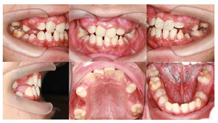

口内检查:全口口腔卫生较差。11、12、22、42未见萌出。

21部分萌出3~4 mm,牙龈缘稍红肿,与31反

,反覆

1~2 mm,反覆盖2 mm。

26、36釉质表面呈黄褐色,质硬、光滑,探及深窝沟,未探及龋坏。

55、16、65、46探及龋坏达牙本质中层,质软,无松动,叩诊(-),根尖区黏膜未见红肿、窦道等异常,扪诊无不适。

治疗结果:总疗程共19个月,矫治后患者上颌双侧中切牙基本牵引至正常位置,左上恒中切牙及左下恒中切牙反

解除,上前牙恢复正常突度及倾斜度,下前牙恢复正常突度,稍舌倾。上下颌切牙覆

覆盖正常。上颌双侧恒尖牙未萌,间隙保留,左上恒尖牙异位好转,牙冠近中向倾斜程度减轻。下颌缺失右侧恒侧切牙,间隙关闭并排列整齐。通过慢速扩弓与及时拔除萌出通道上相应乳牙及多生牙,上下颌前磨牙、磨牙自然萌出到正常位置并建

。埋伏多生牙拔除手术顺利,无术后感染及复发。所有萌出恒牙完成窝沟封闭术。